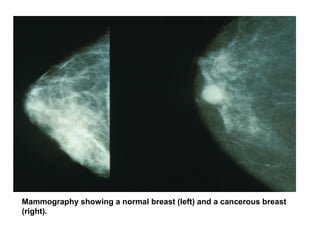

Mammography showing a normal breast (left) and a cancerous breast

(right).

Mammography showing anormal breast (left) and a cancerous breast (right).